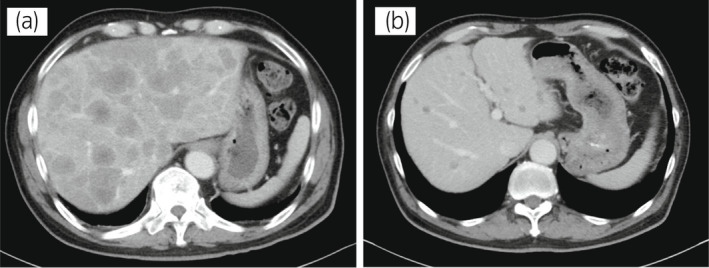

圖1:病例1.順鉑和依托泊苷三個療程前后的腹部CT圖像。 (a) 治療前和 (b) 治療后。